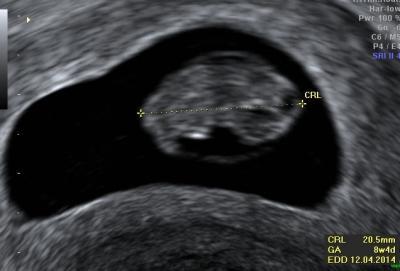

Wooow Das Herz schlägt und es ist 2,5 cm groß :) Es war so unbeschreiblich schön :) jetzt bin ich so glücklich. Alles richtig entwickelt sagt er :) anbei ein Bild :)

Bild zu Wow.. - Forum für April - Mamis

Schönes Fotos. Mein Foto von heute sieht ähnlich aus. Mein Würmchen ist 2,07 cm. groß. Ich hab mich auch gefragt, wo der Dottersack ist. Aber wahscheinlich hätte man ihn aus einer anderen Perspektive gesehen.

Ne Dottersack war da unten rechts erkennt man auf dem Foto nicht. Und die Nabelschnur habe ich gesehen :) geht der Dottersack weg?